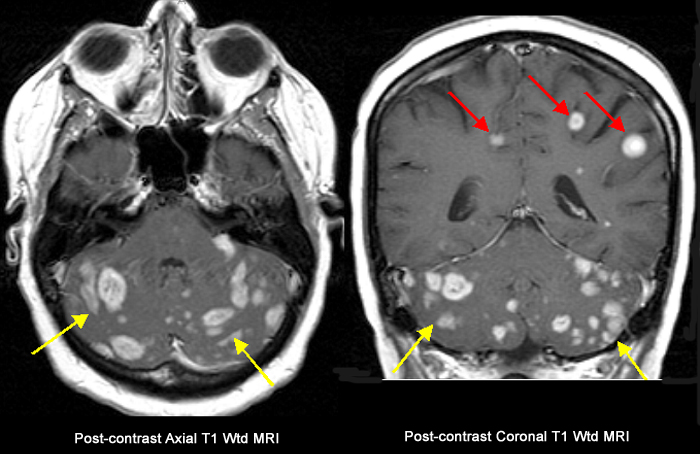

Multiple Metastasis To The Brain From Breast Primary40-year old lady with a history of breast carcinoma diagnosed 6 years ago, presented with headache and ataxia. Findings: Shower of at least 30 metastatic enhancing lesions are seen closely packed together within both cerebellar hemispheres (yellow arrows), and few lesions also seen within both posterior fronto-parietal lobes (red arrows). |